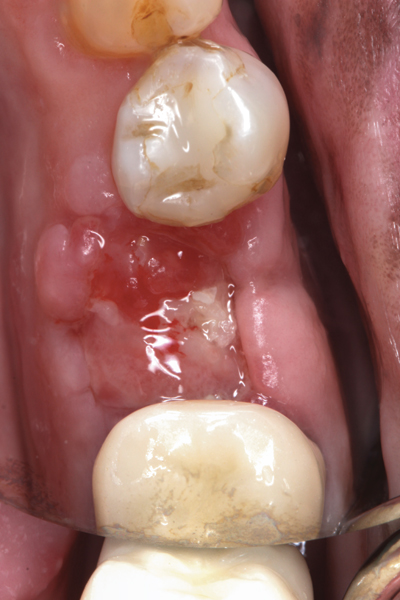

Fig 17. Bone graft was placed in the socket and a d-PTFE barrier was used to cover the graft. The bone graft material was placed beyond the alveolar housing to accommodate shrinkage of graft material and to facilitate attaining a wide alveolar ridge. The barrier was removed after 6 weeks.

Figure 17

Fig 18. Healed ridge exposed after 6 months.

Figure 18